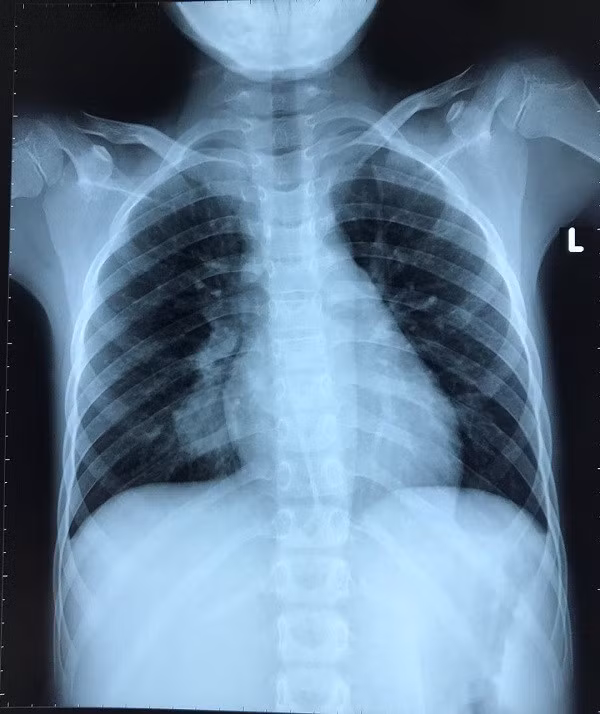

Tuy nhiên, các kết quả kiểm tra, xét nghiệm không ghi nhận dấu chứng của bệnh lao. Kiểm tra hình ảnh bác sĩ nghi ngờ cậu bé có khối u ở phổi nên chuyển sang Bệnh viện Nhi Đồng 2. Tại đây, bệnh nhân được chụp CT-Scan ngực, phát hiện túi phình động mạch phổi ở thùy dưới phổi phải, kích thước 20x18mm.